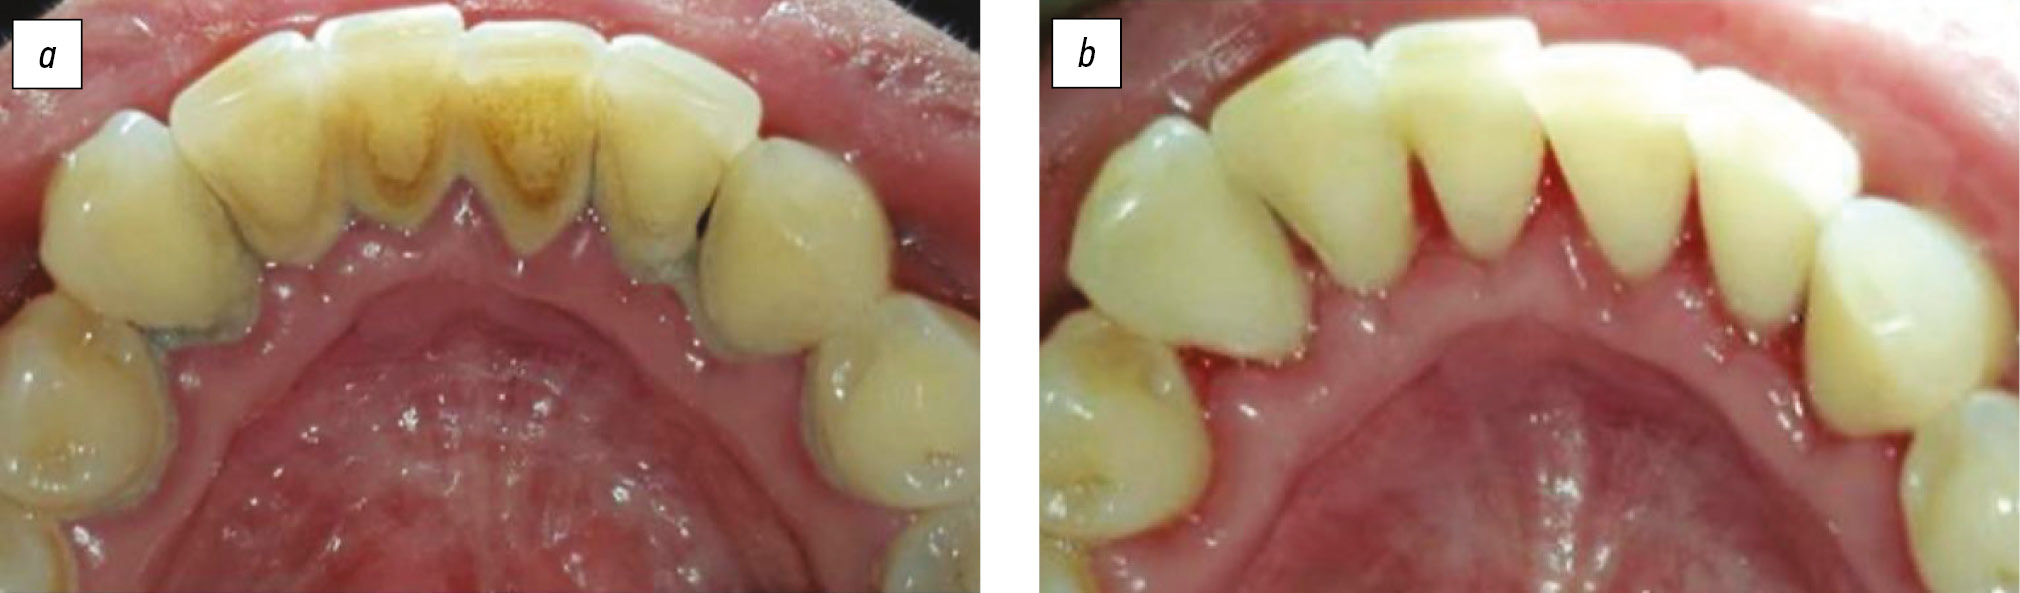

Лечение. Пациентам обеих групп провели профессиональную гигиену зубов и ревизию пародонтальных карманов, сняли над- и поддесневые зубные отложения (рис. 2).

Рис. 2. Зубные отложения: а — до проведения профессиональной гигиены полости рта; b — после профессиональной гигиены полости рта.